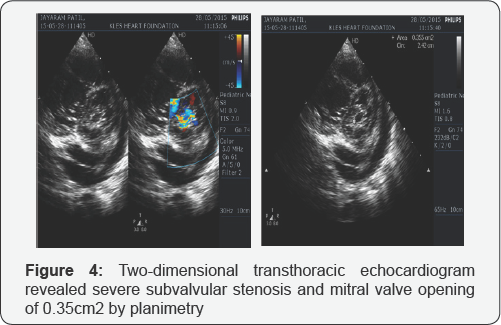

The electrocardiogram (ECG) showed sinus tachycardia with rightaxis deviation (+110°), left atrial enlargement and right ventricular hypertrophy (RVH) (Figure 1). The chest x-ray showed evidence of left atrial enlargement, pulmonary venous hypertension and pulmonary arterial hypertension (Figure 2) . The two-dimensional transthoracic echocardiogram (TTE) revealed thickening and shortening of the anterior and posterior mitral leaflets and chordae, fusion of the commissures with anterior leaflet doming and fixed posterior mitral leaflet (Figure 3) , turbulent mitral inflow jet, severe subvalvular stenosis with peak pressure gradient of 27mmHg, mean pressure gradient of 19mmHg and mitral valve opening of 0.35cm2 by planimetry (Figure 4). The patient also had severe tricuspid regurgitation with peak gradient of 76mmHg (Figure 5) and severe pulmonary hypertension, estimated right ventricular systolic pressure 91mmHg. With all these echocardiographic evidences and clinical condition of congestive cardiac failure, a diagnosis of severe MS and severe pulmonary artery hypertension (PAH) was concluded. The patient clinical condition was initially stabilized by strict bed rest and decongestive therapy with diuretics. After intial stabilization the patient was taken for commissurotomy.